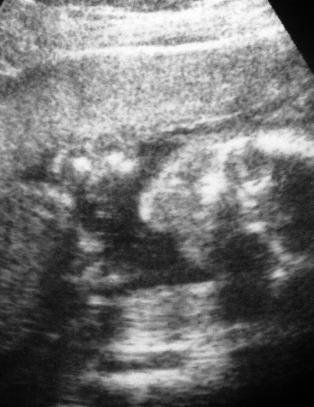

- Få dager skiller fosterne vi aborterer, fra de vi skal satse på og redde livet til

Norske jordmødre måtte abortere nesten seks måneder gamle friske fostere. Les mer

Sykehus gjennomførte abort etter 22. uke

De ansatte som måtte gjennomføre aborten, opplevde det som vanskelig og belastende. Les mer